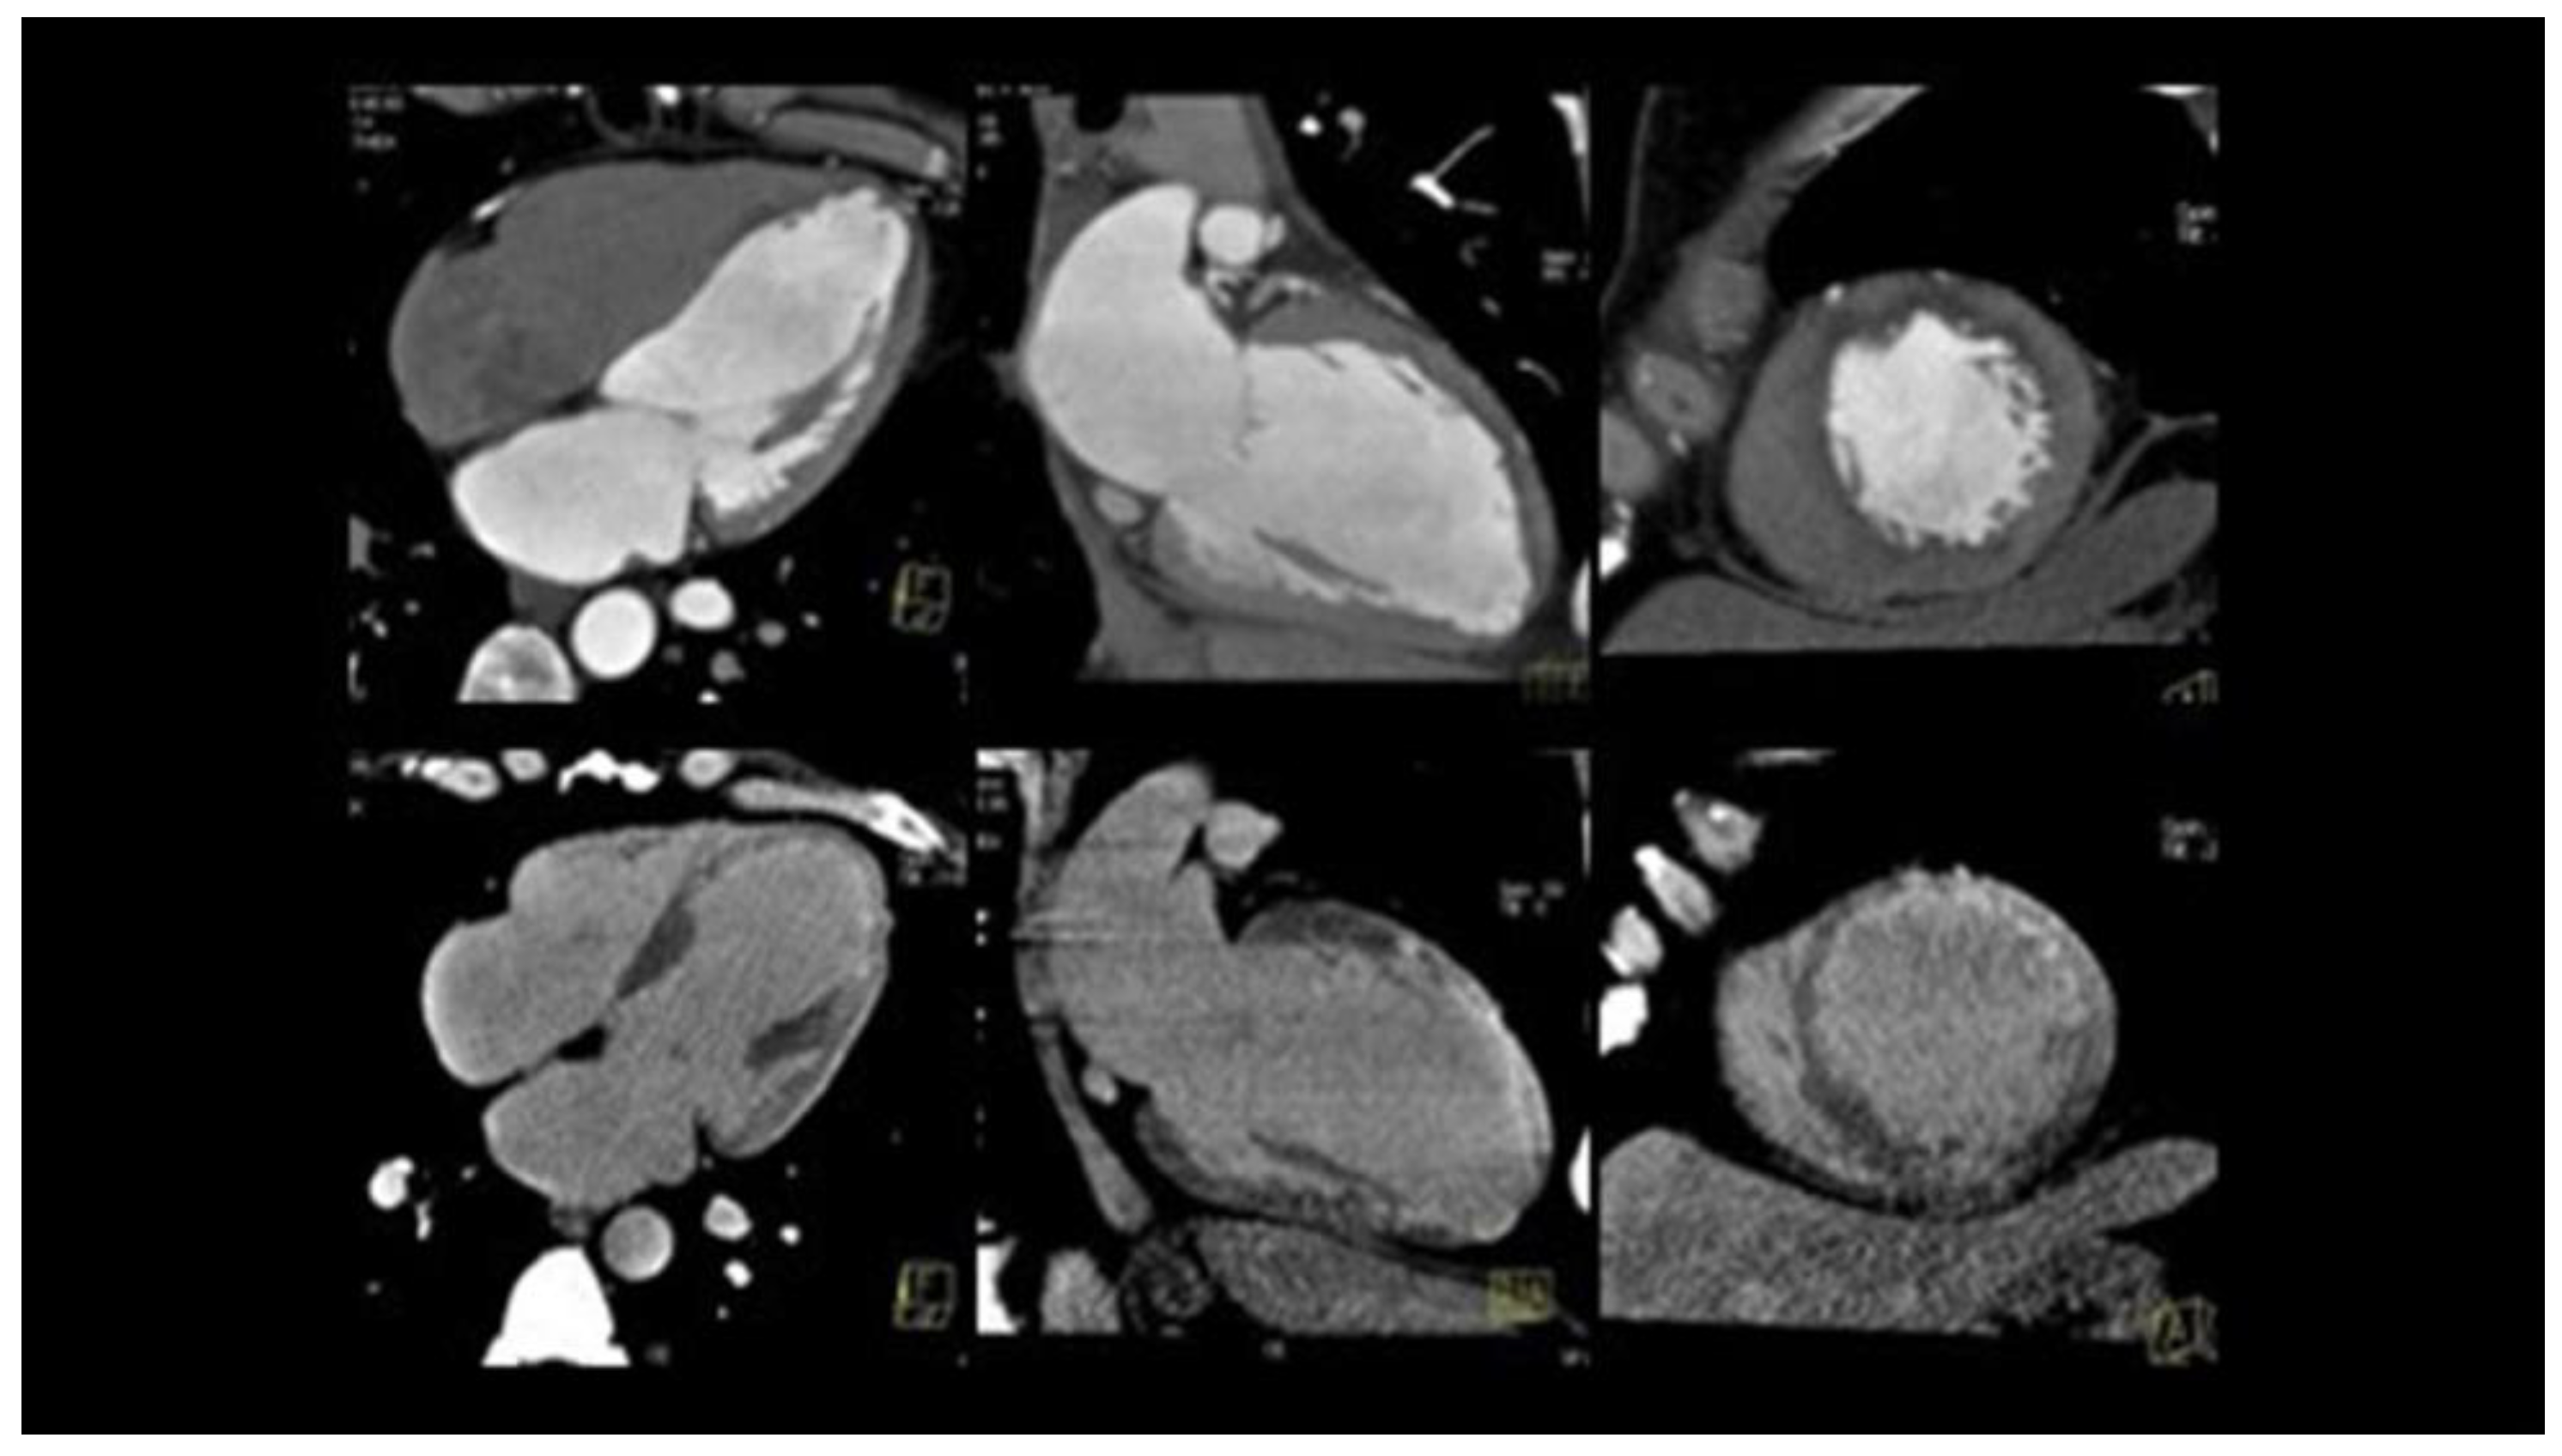

| Coronarography | IVUS | OCT | CCTA | |

|---|---|---|---|---|

| Advantages | Easily executable Images suggestive of SCAD in most cases | Visualization of the intramural hematoma and the flap | Visualization of the vessel wall, the intimate, the false light, intramural hematoma, and any flaps and areas of communication between the true and false lumen | No possibility of iatrogenic damage Image of the presence of contrast in the false lumen Visualization of intramural hematoma |

| Limitations | Invasive Image of the vase light but not the wall | Passage of the guide in the coronary artery No identification of the middle intimal membrane No identification of small areas of connection between false and true lumen | Passage of catheter in coronary artery and injection of contrast at high pressure, with the danger of expansion of the dissection itself | Limited data on its use in acute Absence of specific diagnostic criteria for EXP Frequency-dependent motion artifacts Limited utility for pots < 2.5 mm in diameter Difficulty in distinguishing between non calcified atherosclerotic plaques and intramural hematoma |

| Use | Diagnosis of SCAD | Confirmation of diagnosis | The gold standard method for the confirmation of SCAD | Follow up |